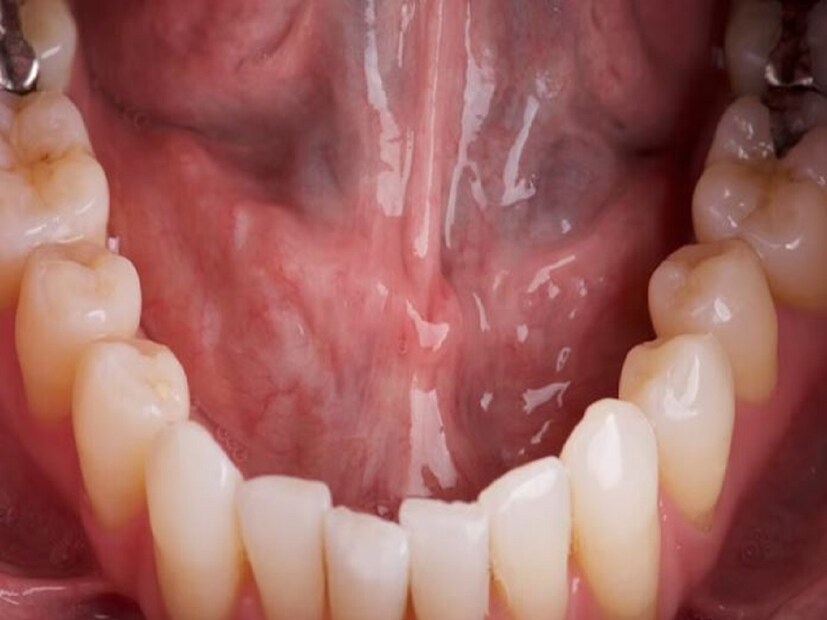

ডাঃ দৌলত সিং জানান, মুখের ক্যানসারের ক্ষেত্রে মুখের ভিতরে সাদা বা লাল দাগ তৈরি হয়। এ ছাড়া দাঁত শিথিল হতে থাকে। মুখের ভিতরে মাংসপিণ্ড গজায়। প্রায়ই মুখে ব্যথা হয়। শুধু তাই নয়, মুখে ক্যানসার হলে কানেও ব্যথা শুরু হয়। যখন সংক্রমণ বৃদ্ধি পায়, তখন খাবার গিলতে অসুবিধা হয়।

রোগ হওয়ার পরপরই লক্ষণ দেখা যায় না। এটি যত পাকতে ষুরু করে, তত তা পরিস্ফূট হয়। জেনে নিন এমন কিছু সমস্যার কথা যা মুখের ক্যানসারের প্রাথমিক উপসর্গ হতে পারে। তাই সমস্যা হলেই দ্রুত ক্যানসার বিশেষজ্ঞের পরামর্শ নিন। প্রাথমিক অবস্থায় ধরা পড়লে মুখের ক্যানসার সম্পূর্ণ ভাবে সারিয়ে তোলা যায়। ঠোঁট, জিভ, গালের ভিতরের অংশ, মাড়ি, মুখের শক্ত ও নরম তালু, গলার নীচের অংশে মুখের এই সব অংশই ক্যানসারে আক্রান্ত হয় বেশি। মুখের ক্যানসারের সাধারণ কিছু উপসর্গ রয়েছে, যা অবহেলা করলে ক্ষতি হতে পারে মারাত্মক। কোন কোন লক্ষণ দেখলে সতর্ক হবেন?